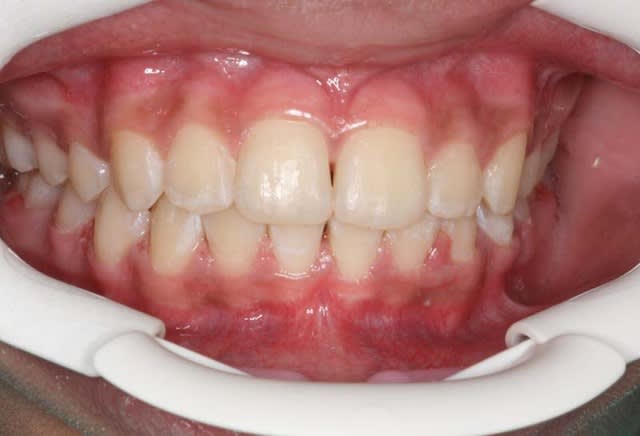

Img 1 xacnga - Eugenol

Img 2 siytdm - Eugenol

Img 3 ituagt - Eugenol

Img 4 r3tw6u - Eugenol

Img 5 z8ak0k - Eugenol

Avant TTT.

à suivre Bjc.